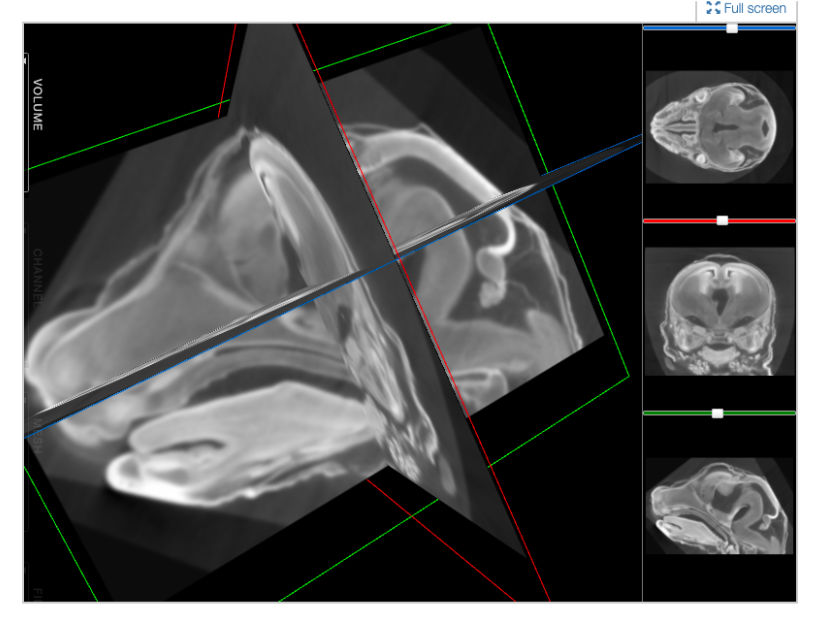

FaceBase is a collaborative NIDCR-funded project that houses comprehensive data in support of advancing research into craniofacial development and malformation. It serves as a community resource by curating large datasets of a variety of types from the craniofacial research community and sharing them via this website. Practices emphasize a comprehensive and multidisciplinary approach to understanding the developmental processes that create the face. The data offered spotlights high-throughput genetic, molecular, biological, imaging and computational techniques. One of the missions of this project is to facilitate cooperation and collaboration between the central coordinating center (ie, the Hub) and the craniofacial research community.